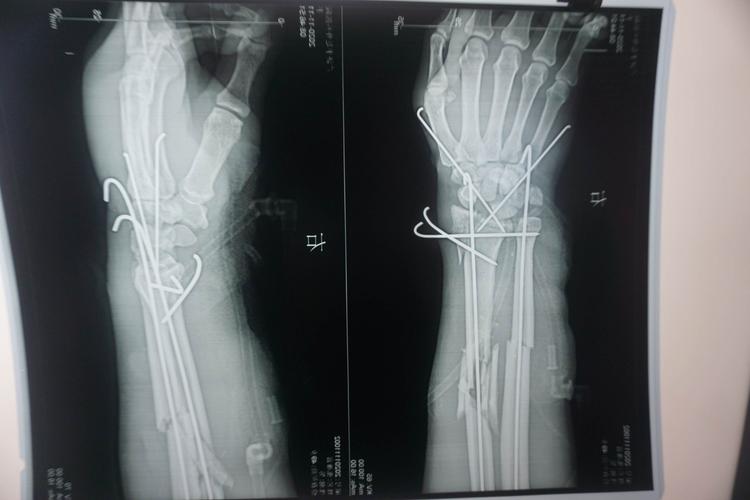

一期修复神经血管,肌腱,彻底清创,尺桡骨及腕部克氏针固定!

腕关节克氏针固定大体像.